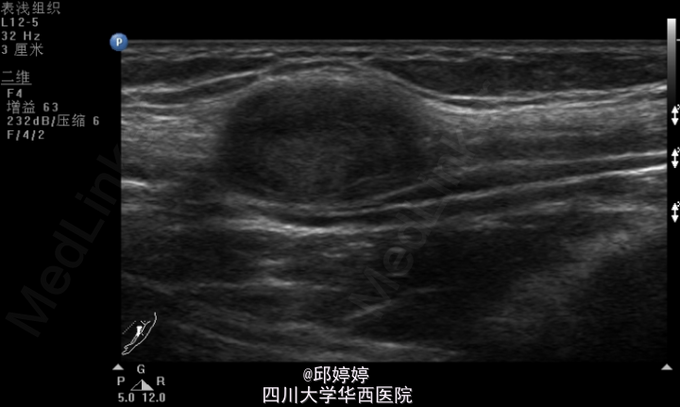

视:左上臂无明显畸形及肌萎缩,肌力5级。无色斑、窦道。触:左上臂近端肱二头肌内侧正中神经可摸及约蚕豆大小的肿物,压痛,并向左上肢及中指放射,活动度不大,与正中神经粘连,Tinner征阳性。动量:左肩、肘、腕关节活动自如。辅助检查:左上肢包块彩超:左上臂包块处查见大小约25*11*16mm的弱回声团,边界清楚,该团块与正中神经相连,内未见明显血流信号(图1,2)。超声诊断提示:左上臂实性团块:神经源性肿瘤?